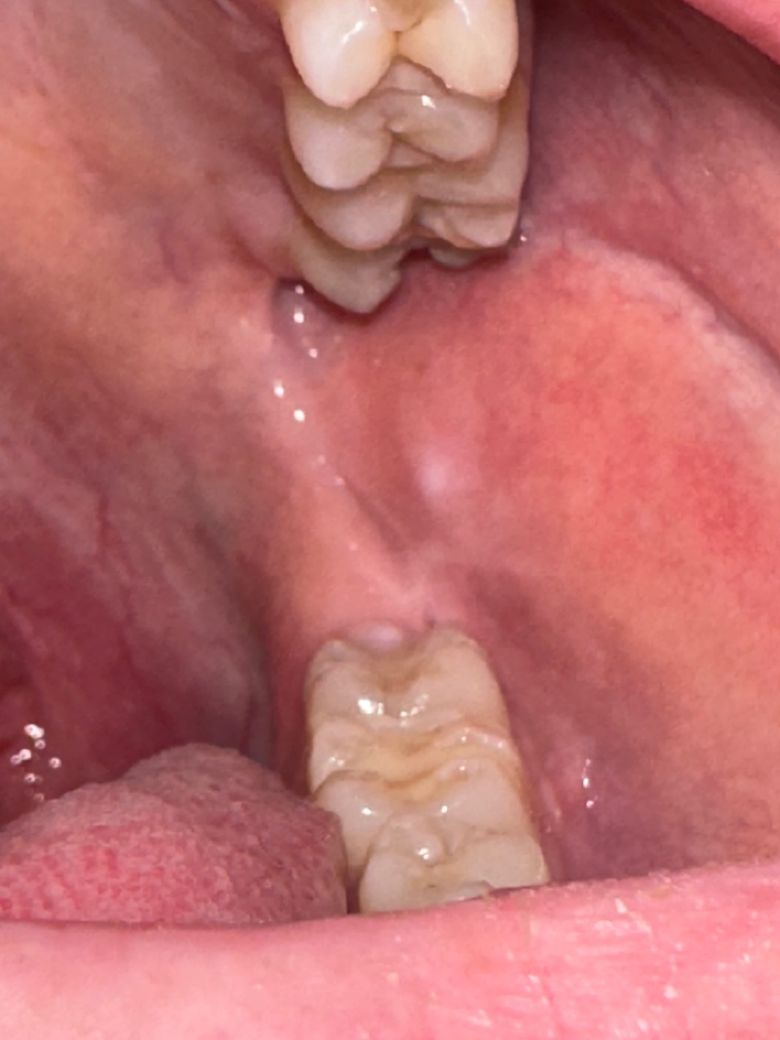

• 2번 째 사진

구내염이 치유된 자리에 하얀 흔적이 남은 것으로 보입니다.

사진에서 피막을 형성하는 것처럼 보이지 않으며, 두드러지게 융기되어 있거나 구진(papula)를 형성하지도 않은 것처럼 보입니다.

또한 궤양성 병소도 아니며 통증성 병소도 아닙니다.

따라서 구내염에서 갓 회복한 새로운 구강 점막 조직으로 추측합니다.

피부에 상처가 났다가 새 살이 돋으면 새로 돋은 살은 주변과 색이 살짝 다른 것을 연상하면 좋을 것 같습니다.

구강암과의 연관성은 떨어져보입니다.